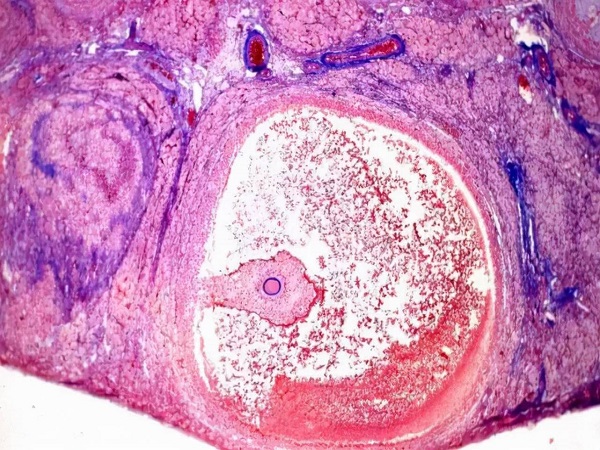

雌二醇是一种由卵泡分泌的雌激素,所以通过雌二醇的多少就能够看出卵泡的质量,一般认为雌二醇的值越高,那么卵泡的质量就越好。但是雌二醇的值并不是判断卵泡质量的唯一标准,一般还需要结合B超检查对卵泡的大小、形态进行综合判断才能够确定卵泡的质量。

众所周知,雌二醇的值和卵泡的质量有一定的关系,往往认为女性体内的雌二醇水平越高越适合卵泡的生长发育。如果女性体内的雌二醇水平降低,就会直接影响卵泡的生长,进而导致卵泡质量下降。如果女性想要通过雌二醇了解卵泡的质量,最好是在月经干净后去医院抽血查雌二醇的值。

雌二醇值越高说明卵泡质量越好